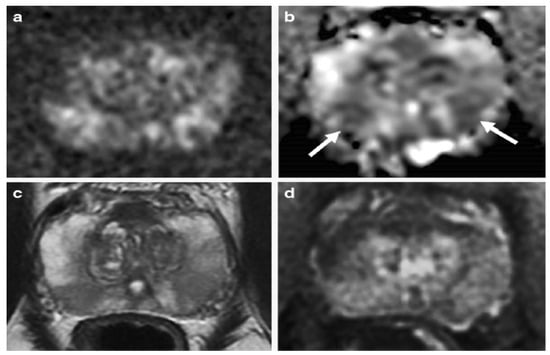

Various studies have used mp-MRI to diagnose PCa and have noted its diagnostic performance. Two examples of mp-MRI diagnostic performance are shown in Figure 1 and Figure 2 [34]. Di Campli et al. [35] conducted a study on mp-MRI to determine the diagnostic accuracy of PCa. A total of 85 patients underwent prostate MRI investigation at a 1.5 T MR system without an endorectal coil. In this study, the MR images were separately interpreted by three radiologists with 7 (reader 1), 3 (reader 2) and 1 year(s) (reader 3) of experience in prostate MRI, respectively (according to Prostate Imaging Reporting and Data System (PI-RADS) version 2). The sensitivity (CI 95%), specificity (CI 95%), area under the curve (AUC), and accuracy values for readers 1, 2, 3 were obtained (97.2% (90.3–99.7%), 88.9% (79.3–95.1%), 83.3% (72.7–91.1%)), (61.5% (31.6–86.1%), 23.1% (5–53.8%), 46.2% (19.2–74.9%)), (0.72, 0.70, 0.54), and 90.58, 78.82, and 77.64, respectively [35].

Figure 1. An example of mp-MRI diagnostic performance in a 66-year-old man with PSA 9.1 ng/mL. A focal low signal (arrow) in the midline apex TZ, (a) but there is not a high signal on the DWI, (c) or low signal on ADC maps (d). An early and clear enhancement on the DCE-MRI (arrow) in the midline apex TZ (b) was recognized as a high-possibility lesion. This lesion was proven by targeted transperineal biopsy (Gleason 5 + 4). “Reprinted with permission from Ref. [34]. 2020, Springer”. More details on “Copyright and Licensing” are available via the following link: https://link.springer.com/article/10.1007/s00330-020-06782-0 (accessed on 12 March 2020).